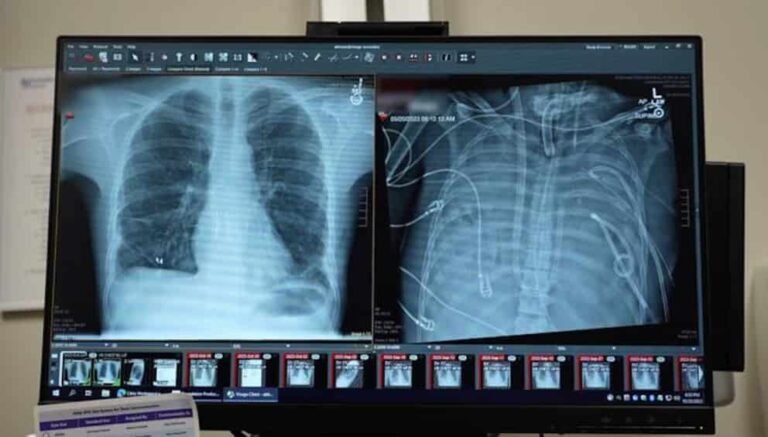

RespiratoriasVigilancia estacional activaCOVID-19, influenza y virus respiratorios siguen bajo seguimiento regional.

CrónicasAlta carga sanitariaCardiovasculares, diabetes y cáncer sostienen presión asistencial global.

Etiqueta: cuidados críticos